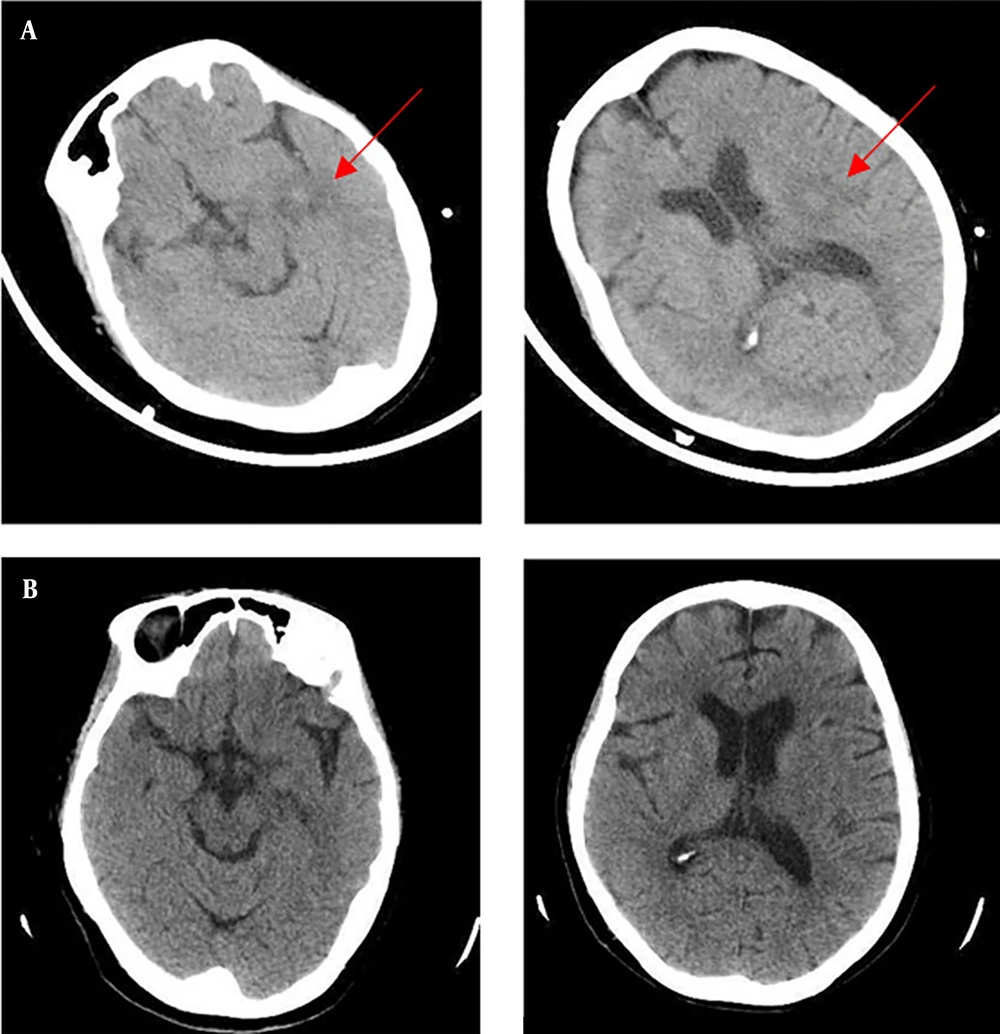

A 72-year-old woman was admitted to our emergency department of Zhejiang Hospital due to a 5-day history of fever and a 7-hour delirium, accompanied by progressive dyspnea, on November 22, 2021. She presented with a high fever 5 days before admission. The peak temperature was 40°C, with dry cough and mild headache. She was observed to have stumbled 2 days ago (not fallen down) and was sent to the local hospital by family members. Laboratory data in the local hospital revealed a white blood cell (WBC) count of 3.92 × 109/L with an elevated neutrophil ratio of 93.9%. The concentrations of C-reactive protein (CRP) and procalcitonin (PCT) were 308.9 mg/L and 3.585 ng/mL, respectively. Erythrocyte sedimentation rate (ESR) was 73 mm/h. A head computed tomography (CT) scan showed multiple nodules with peripheral edema in the left cerebral hemisphere (November 20, 2021, Figure 1A). A chest CT scan indicated an extensive inflammatory lesion with partial consolidation in the left upper lung (November 20, 2021, Figure 2A). After the poor response to the therapy of cefoperazone/sulbactam, antipyretic and fluid infusion, she came to our emergency.

The patient was diagnosed with a severe C. psittaci infection, both pulmonary and extrapulmonary, including bloodstream infection and central nervous system infections. Therefore, azithromycin was switched to doxycycline on day 2 (100 mg, every 12 hours, oral). Piperacillin/tazobactam continued for prophylaxis therapy in spite of the negative results of gram-negative bacteria. Body temperature returned to normal, dyspnea was relieved, and consciousness went back to normal after 48 hours of treatment. In accordance with temperature, the neutrophil predominance dropped continuously, along with CRP, PCT, and ESR. The head CT scan showed no findings of acute infection or cerebral hemorrhage on day 5 (Figure 1B).

In this study, the central nervous system manifestations in the patient are posited to represent a vascular inflammation underpinned by cell-mediated immunity incited by the parasitism of Chlamydia within the cerebral blood vessels. After antibiotic intervention, a consequential impediment in the transition of Chlamydia from its EB to reticulate bodies RB is observed, thereby arresting their inherent intracellular maturation. Consequently, a subsequent head CT scan reveals the prompt resorption of the lesions. In addition, she had a special PE complication. Several cases of C. psittaci infection complicated with lower limb arterial occlusion with or without cardiac involvement have been reported earlier (10); however, similar reports are rare. Whether PE is associated with psittacosis infection remains to be determined.